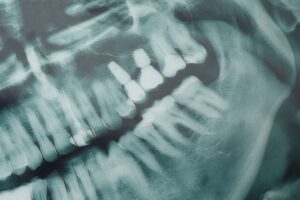

Dental implants in Carbondale, IL, have revolutionized the field of restorative dentistry, offering a reliable and aesthetically pleasing solution for tooth loss. These dental prosthetics function as artificial roots, creating a strong foundation for replacement teeth that look, feel, and work like your natural ones. Apart from the obvious aesthetic advantage, dental implants also play a key role in maintaining oral health. They prevent bone loss in the jaw, maintain the alignment of remaining teeth, and ensure proper bite function.

Zygomatic and endosteal implants are two distinct types of dental implants used in different clinical situations. Zygomatic implants are longer than traditional implants and are anchored in the zygomatic bone (cheekbone) rather than the jawbone. These implants are often used for patients who have severe bone loss in the upper jaw and do not have enough bone to support regular implants. In contrast, endosteal implants are the most common type of dental implant, typically placed directly into the jawbone.

They are ideal for patients with adequate bone density in the jaw and are available in various shapes, such as screws, cylinders, or blades, to fit the patient's needs. Both types of implants offer solutions to restore missing teeth, with zygomatic implants being a specialized option for those with insufficient upper jawbone structure.